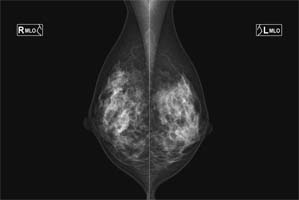

マンモグラフィ検査

乳房のX線写真を撮影します。乳腺を写し出すための乳房専用の装置で検査を行います。検査は、「検診マンモグラフィ―撮影認定資格」を有する女性放射線技師が担当しています。